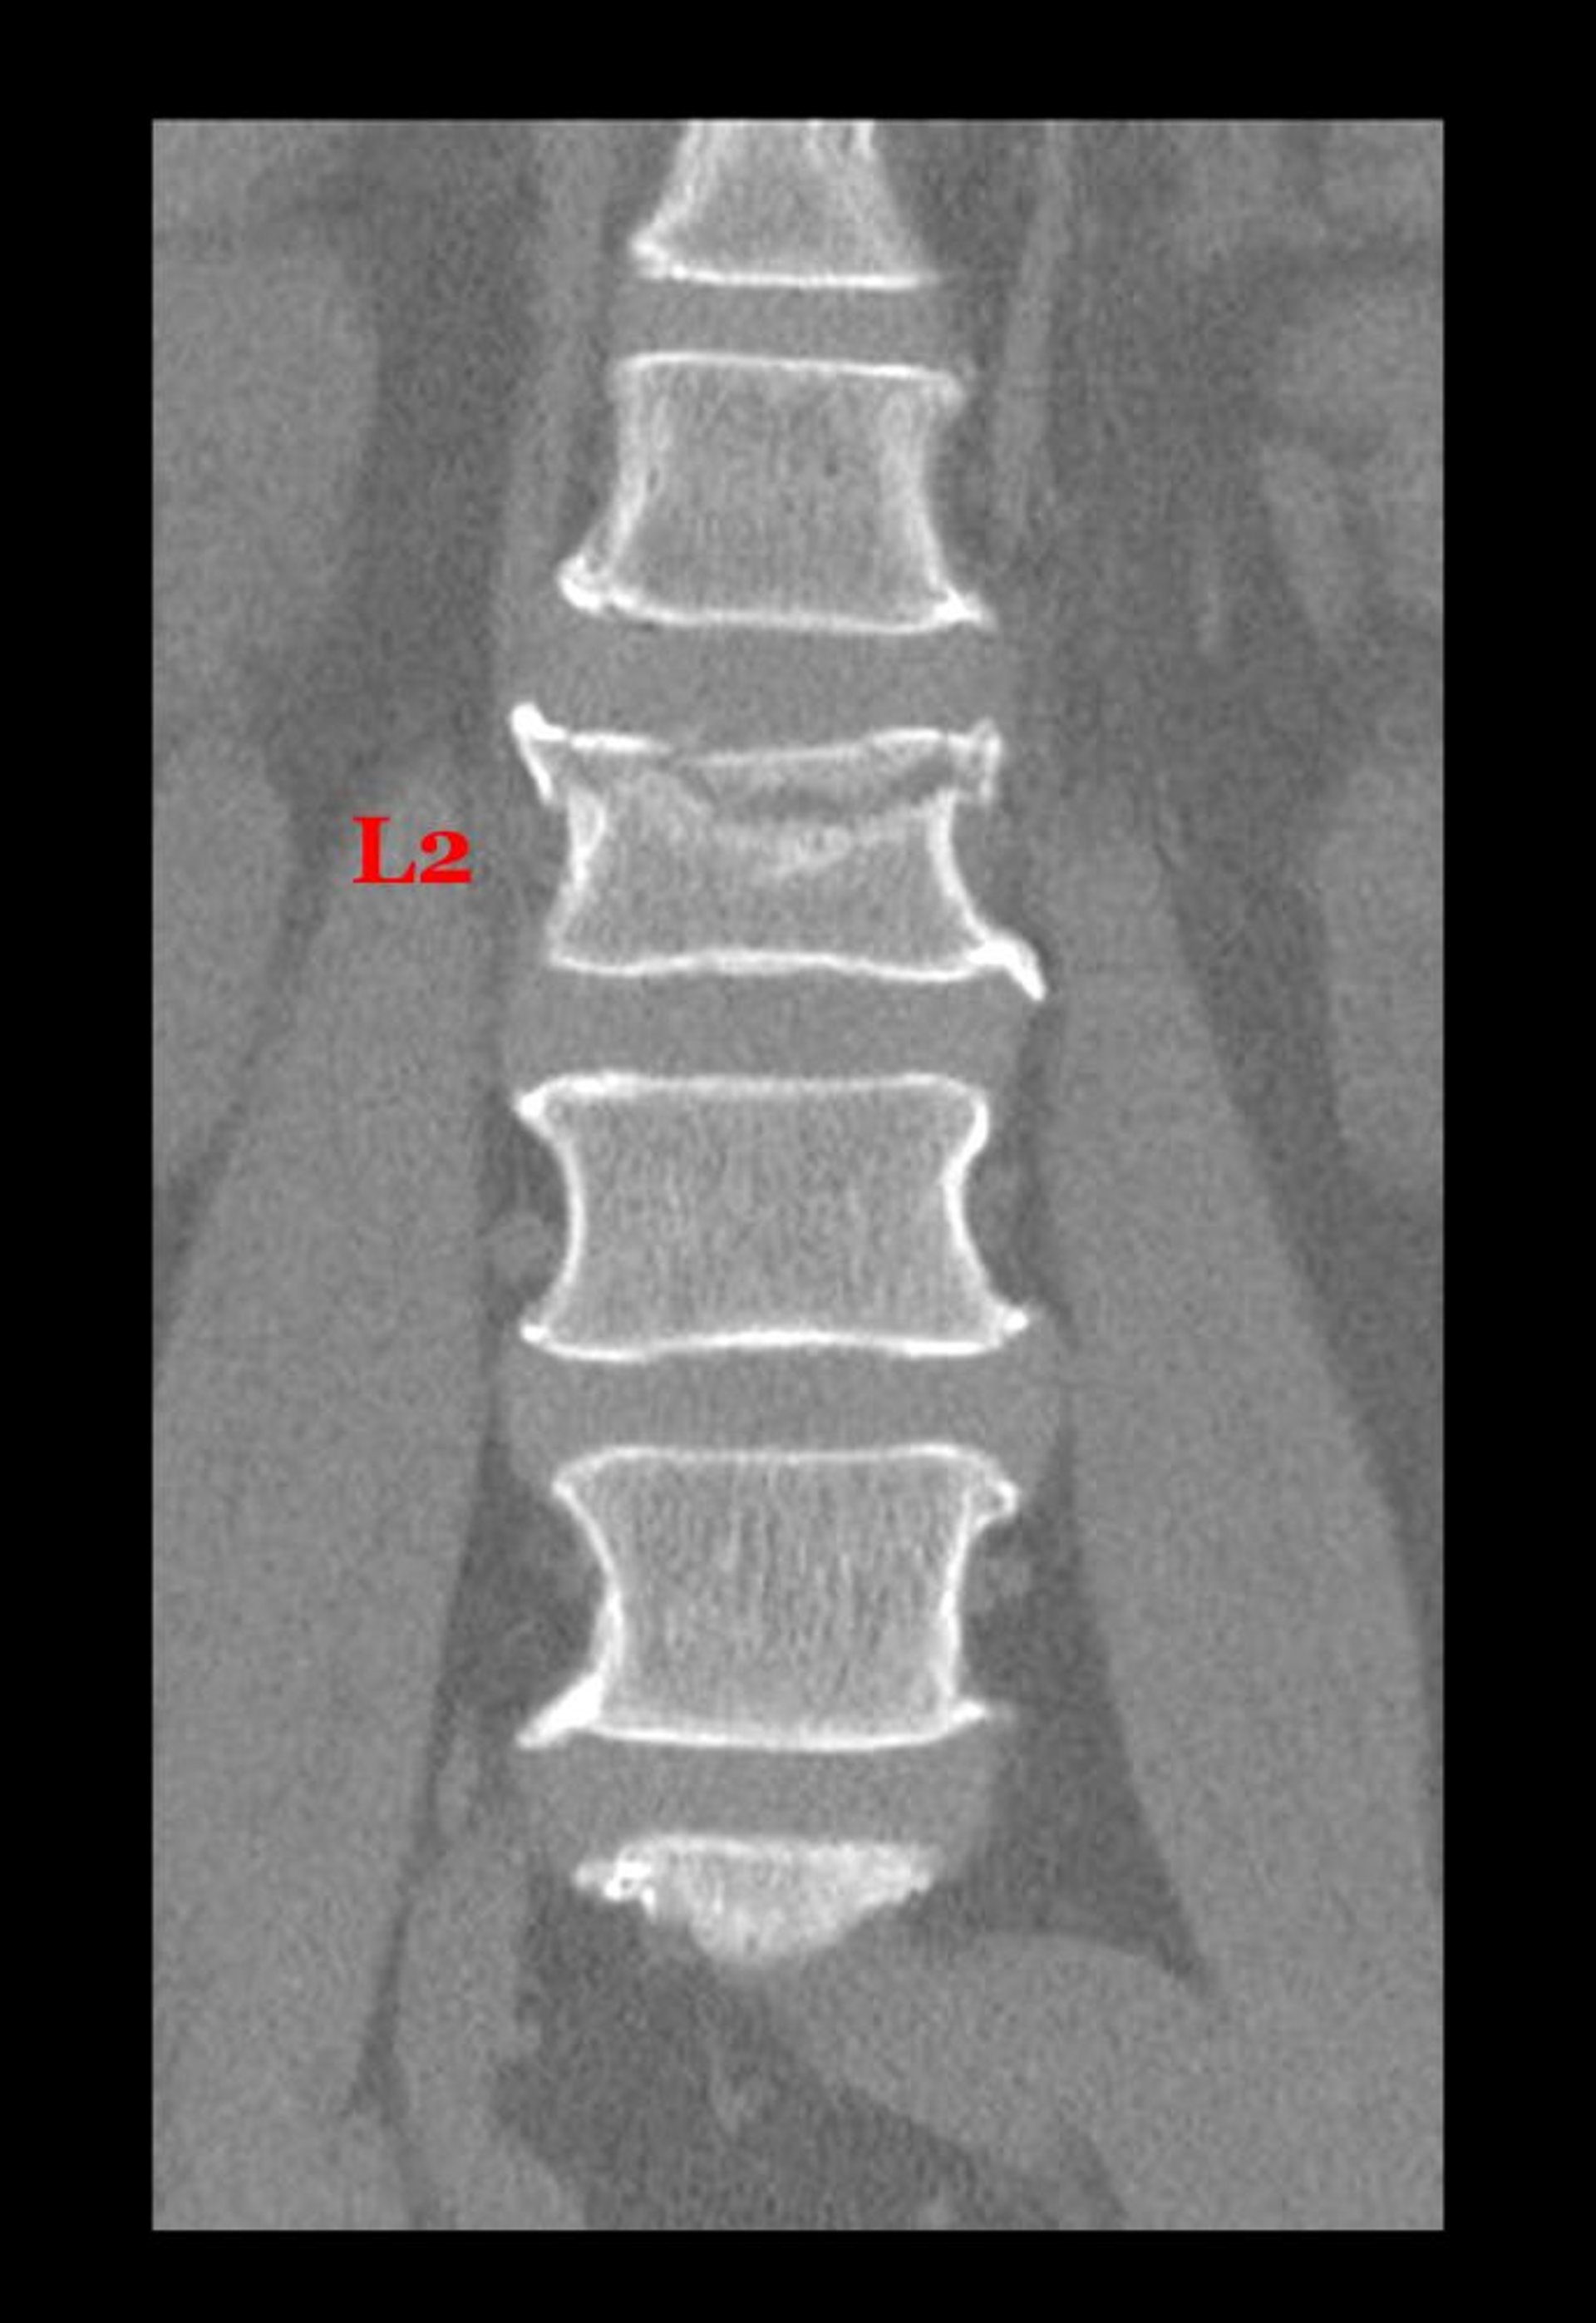

Compression Fracture of a Lumbar Vertebra

This coronal (frontal) view from a CT shows a fracture through the superior aspect of the body of the 2nd lumbar vertebra.